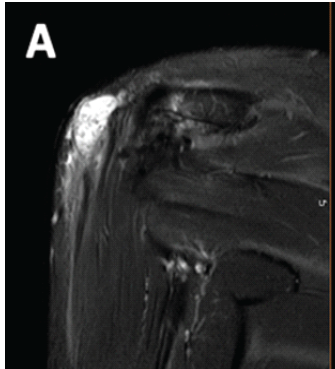

Arthroscopic Fixation of Acute Reverse Bony Bankart Lesion using Cancellous Cannulated Screws: A Rare Case Report

Rahul Kakran , Ashish Kumar Agarwal , Vinay Sharma , Vipin Tyagi , Kamappa Rajappa Binduvaraprasad

………………………………p.255-261